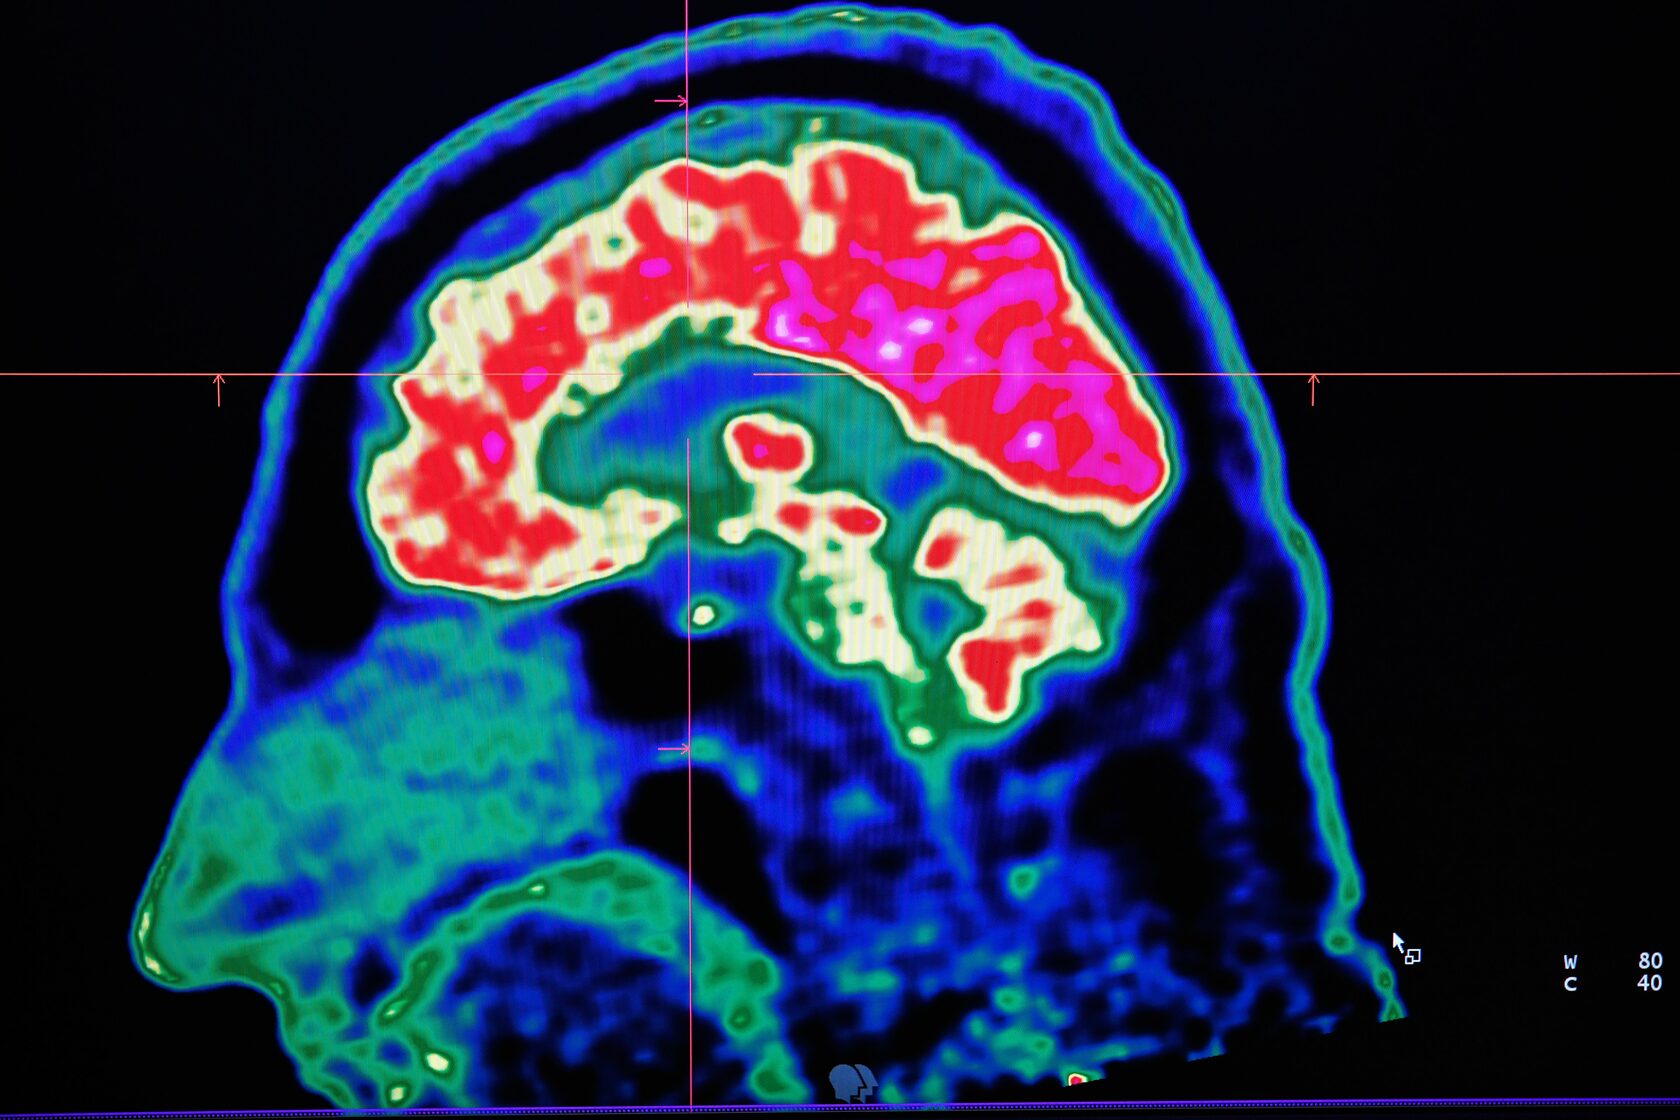

Исследователи применили фокусное ультразвуковое воздействие при помощи прибора ExAblate-Neuro-Type2 (Insightec) под МРТ-навигацией в реальном времени для повышения проницаемости гематоэнцефалического барьера для крупных молекул. При проведении исследования оценивалась концентрация бета-амилоида, меченного 18F-флорбетабеном на ПЭТ.

Несмотря на "пилотный" масштаб исследования, проведенного всего на 3 пациентах, во всех трех случаях было продемонстрировано значительное снижение уровней бета-амилоида при применении фокусированного ультразвука для повышения проницаемости ГЭБ по сравнению с инфузией без данного воздействия.